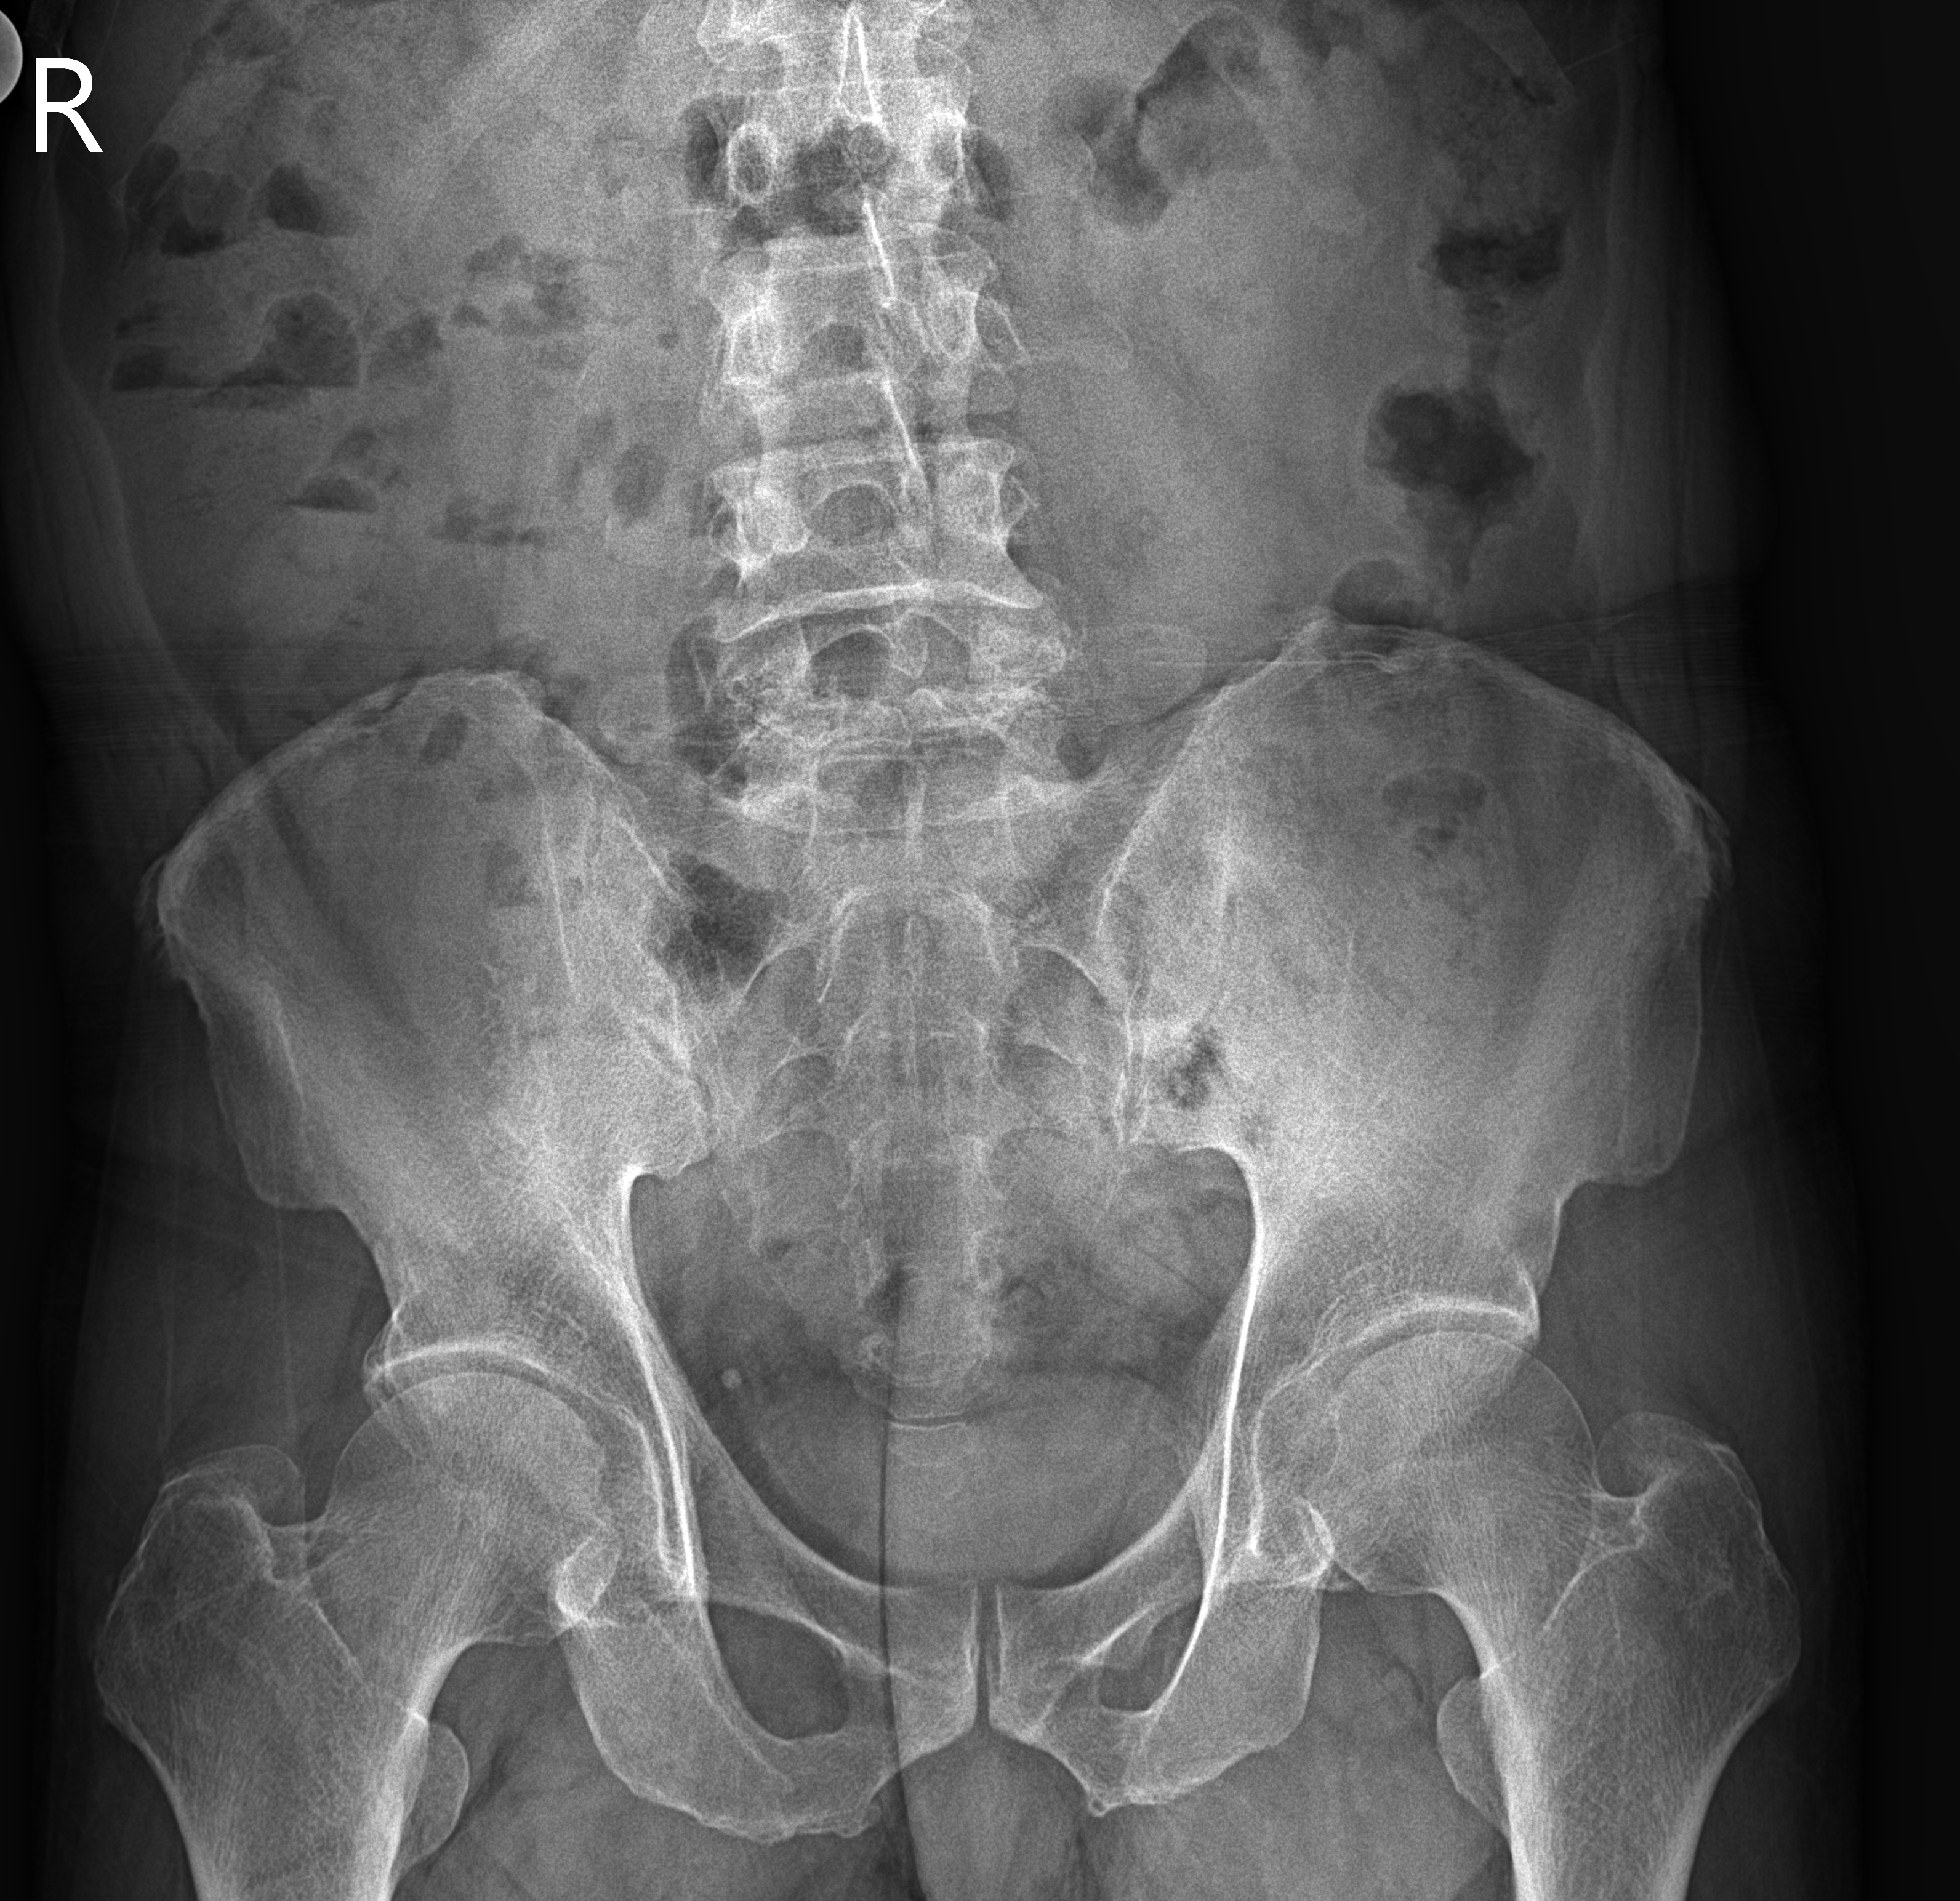

병명: 척추 골절(척추 이분증)

X-Ray 촬영: 서초성모정형외과